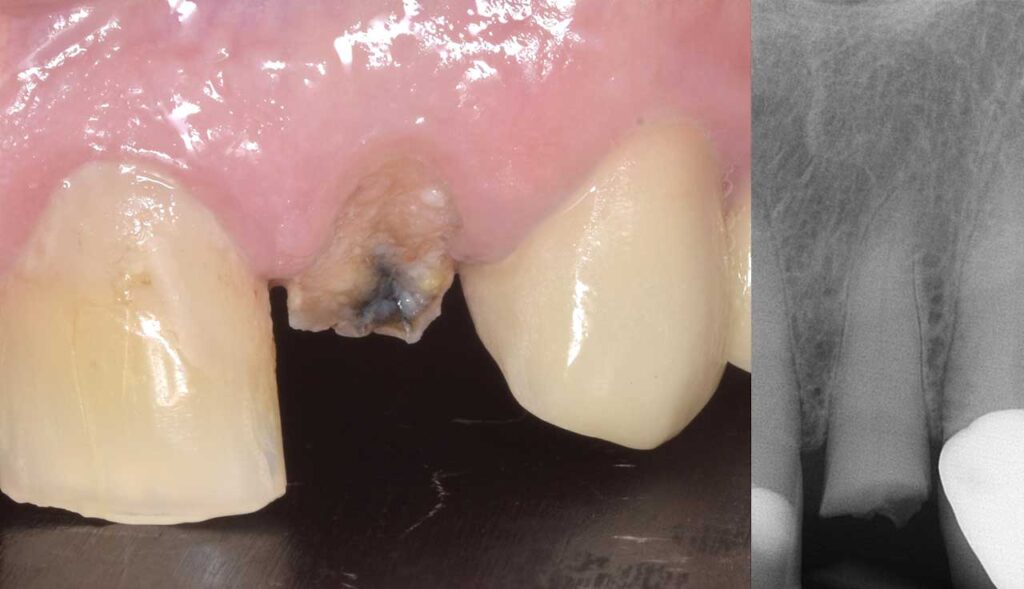

治療前

前歯部インプラント

治療後

折れてしまった歯を抜去し、周りの歯に調和したインプラント治療を行いました。